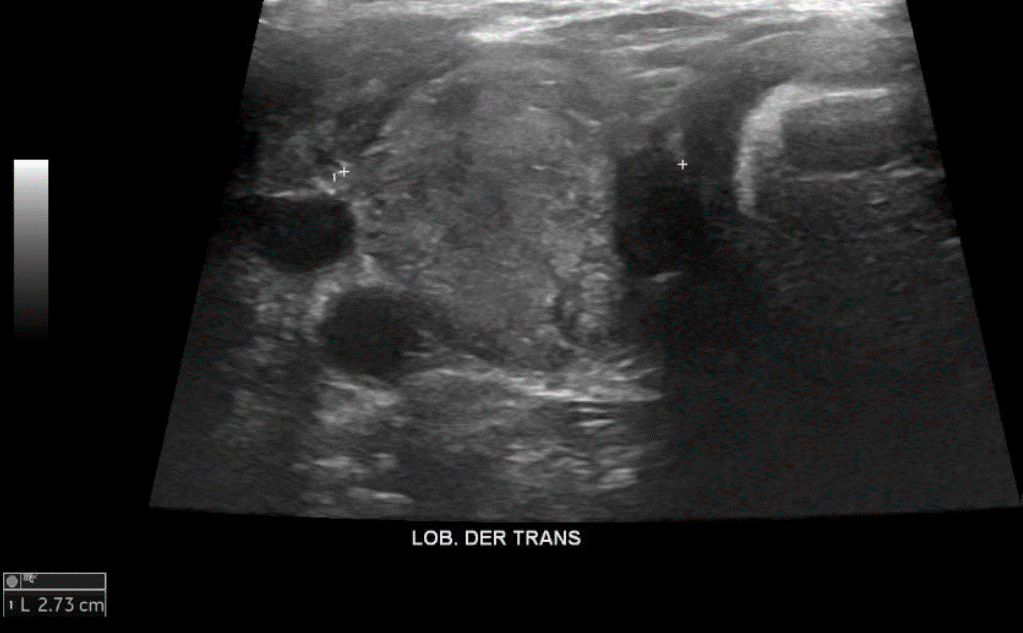

• Tiroides de parénquima heterogéneo, bordes irregulares, tamaño/vascularización conservada en LTI, no así LTD aumentado de tamaño/vascularización a expensas de los nódulos (3). → Bocio Multinodular

• En la Reg Cerv Der GIII se visualiza imagen de aspecto nodular sólida de gran tamaño, heterogénea con pequeñas imágenes hiperecogénicas puntiformes internas, bordes parcialmente definidos con señal interna/periférica al Doppler Color. Se visualizan imágenes de similares aspectos en Reg Cerv Izq GIII y GV. Signos sugerentes de extensión extra tiroidea de probable nódulo de aspecto maligno en LTD.

En el lóbulo tiroideo derecho lesión nodular ecogénica de 19 x 18 mm diámetro calcificada con sombra acústica posterior. Otra lesión nodular hipo ecogénica heterogénea en el polo inferior lóbulo derecho de 16 x 10 x 20 mm y otra de 11 x 11 x 10 mm, esta última con focos ecogénicos puntiformes sugerentes de calcificaciones. Adyacente al lóbulo derecho, lesión nodular hipo ecogénica heterogénea, de 27 x 60 x 23 mm, con focos ecogénicos sugerentes de calcificaciones. Glándulas submandibulares y parótidas de morfología normal. Linfonodos inespecífico en el grupo uno de 6 x 4 mm.